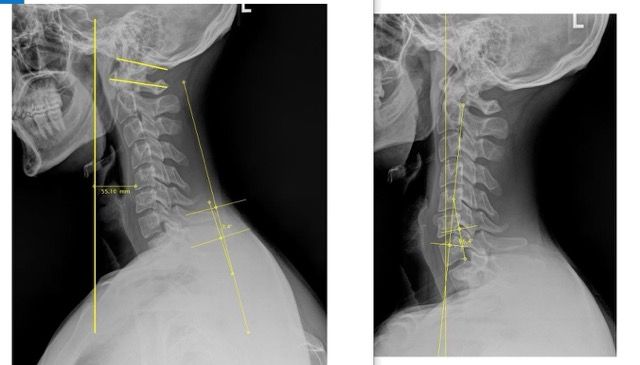

We use detailed X-rays to measure the exact position of your head in relation to your spine. This gives us a clear starting point and allows us to track your improvement with objective measurements.

We take follow-up X-rays to show you exactly how your spine is changing. The images don't lie - you'll see real structural improvement, not just temporary relief.

Our before and after X-rays show dramatic improvements in neck curve and head positioning. What many people think is a permanent problem can actually change with the right care.